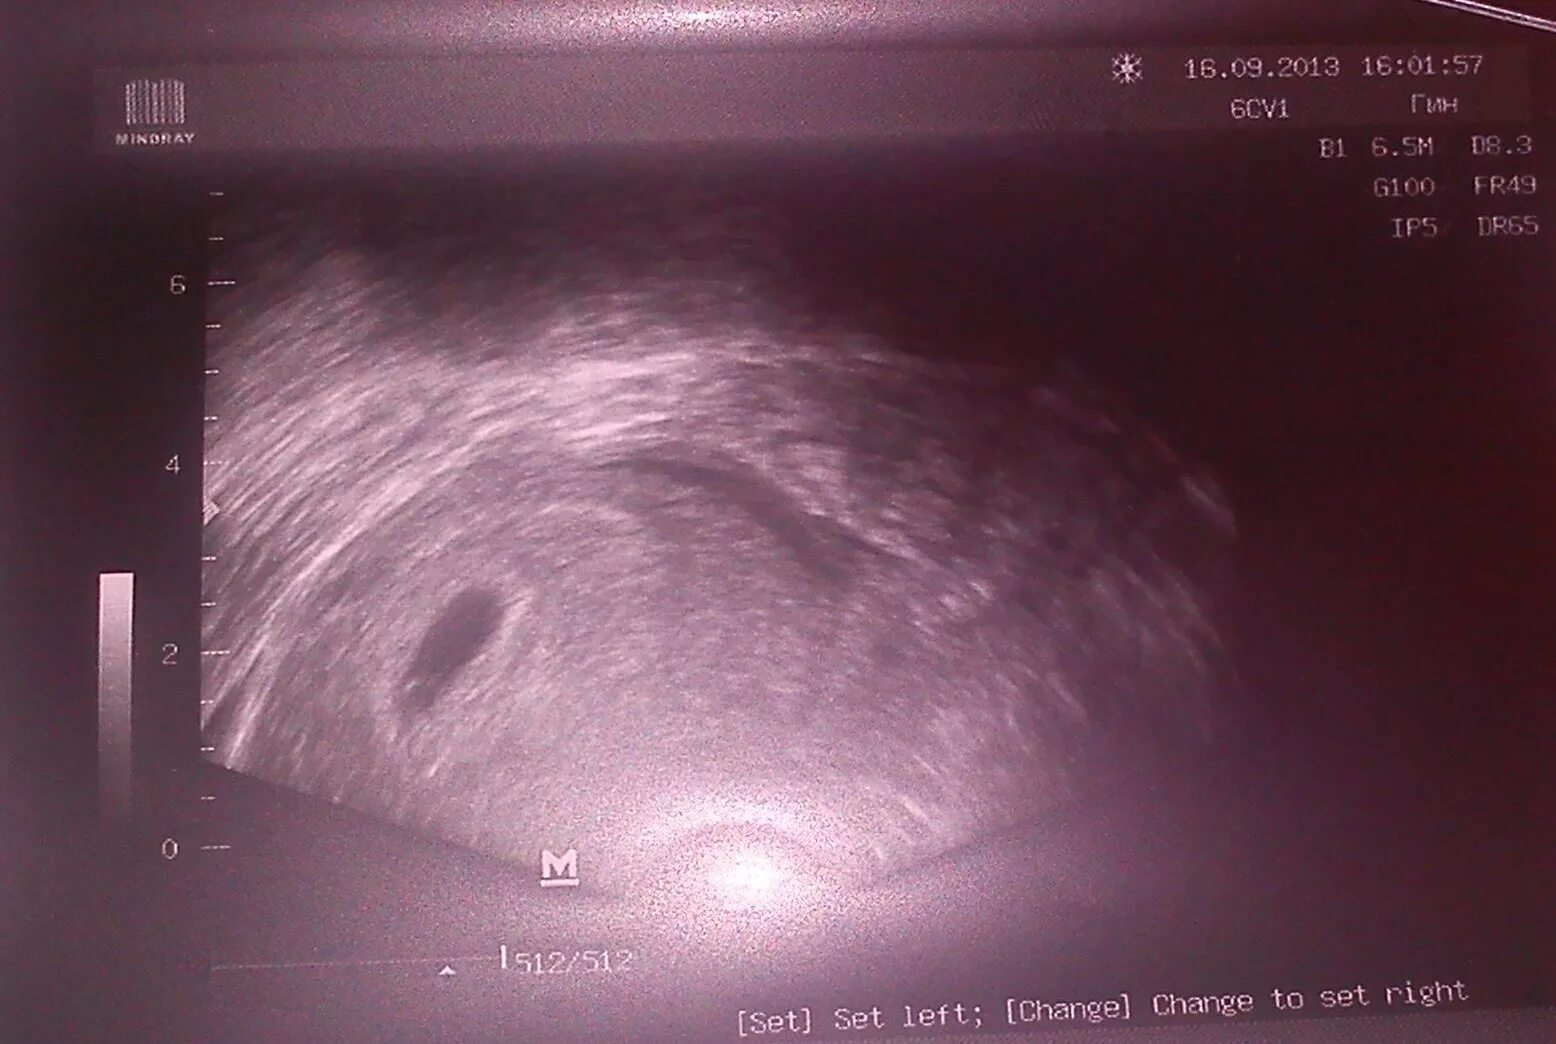

На каком сроке увидели плодное яйцо